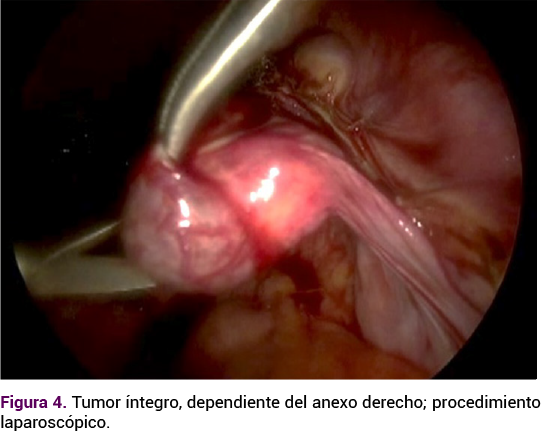

El caso se comentó con todos los integrantes del servicio y se decidió la laparoscopia con: histerectomía total con resección del tumor anexial. Durante la cirugía, en un primer tiempo, se efectuó la histerectomía, sin contratiempos. En el anexo derecho se apreció un tumor de 3 x 2 cm, de bordes bien definidos, móvil, con vasculatura superficial aumentada, sin focos de necrosis o sangrado. La apertura de la tumoración se hizo con corte frío y se encontró tejido friable. La escisión del tumor fue total, con aplicación de endo-loop en la base, con adecuada hemostasia y extracción del tumor por medio de una endobolsa.

Figura 4. Tumor íntegro, dependiente del anexo derecho; procedimiento laparoscópico.